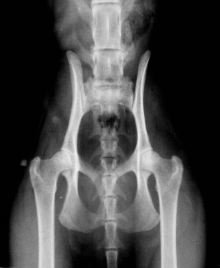

Dysplasie de la hanche (HD)

- Quand on entend parler de dysplasie des hanches et de radiographies, la plupart du temps il s’agit de chiens. Mais ce problème existe aussi couramment chez le chat. La dysplasie des hanches est une malformation héréditaire de l’articulation de la hanche (du pelvis) lorsqu’elle n’est pas assez profonde. A cause de cela, l’os ne se place pas comme il faut dans l’articulation, et un frottement des deux s’ensuit, ainsi qu’une dégénérescence du cartilage. Peu à peu le cartilage disparaît, laissant une surface articulaire d’os à os qui provoque des douleurs. Le corps ne peut produire du cartilage, et tente de se défendre en produisant encore plus de matière osseuse, ce qui ne fait qu’aggraver le problème.

Recommandations pour tester et élever des Maine Coon

Le protocole d’évaluation est comme suit:

- Normal: Bonnes hanches, pas d’anomalies

- Borderline: structure pas tout à fait parfaite mais pas de dysplasie prononcée

- Grade 1: la forme la plus légère de dysplasie

- Grade 2: dysplasie moyenne

- Grade 3: dysplasie sévère

Des généticiens nous ont conseillé de ne pas sélectionner une trop petite population de chats reproducteurs au début de notre étude. Il n’est pas avisé d’exclure complètement tous les chats avec un signe de dysplasie des hanches d’un programme d’élevage. Aussi, nous recommandons aujourd’hui de ne pas automatiquement écarter de l’élevage des chats avec un résultat de test « niveau 1 » sur l’échelle utilisée en Suède, mais de ne croiser ces chats qu’avec des individus ne montrant aucun signe de dysplasie (résultat «normal »).

La dysplasie des hanches chez le chat est une malformation héréditaire due à un ensemble de gènes. Deux chats avec aucun signe de dysplasie peuvent produire un sujet qui développe une dysplasie des hanches. Deux chats atteints de dysplasie peuvent aussi produire des chatons ne montrant aucun signe. Aussi, devrait-on tester une population de reproducteurs à chaque génération pour minimiser le risque du développement de la dysplasie des hanches.